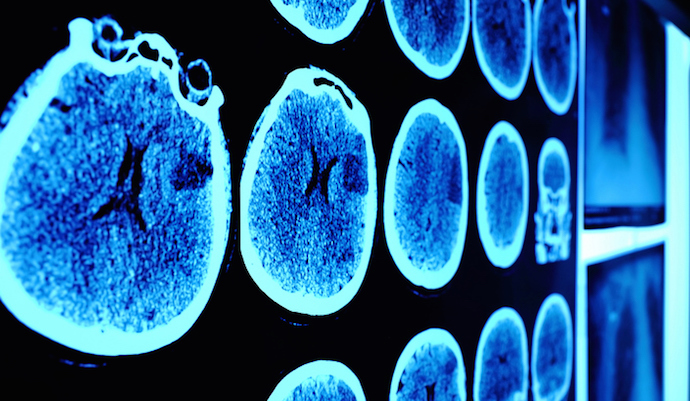

Жасанды интеллект томография арқылы түсірілген суреттегі адам көзіне көрінбейтін өзгерістерді анықтап, осы суреттерді иммунотерапияның 3 кезеңінен кейін салыстырады.